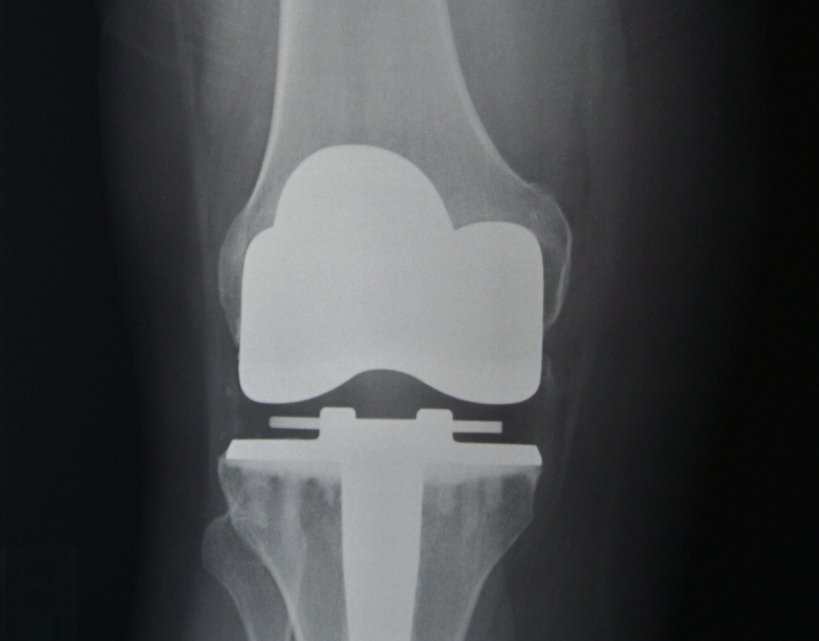

En que consiste y las posibilidades de la cirugía protésica?

En este tipo de intervenciones se reemplaza unas superficies articulares dañadas de la cadera (fémur y pelvis ) por otras superficies artificiales.

Esta técnica fue diseñada con el objetivo de perfeccionar la colocación anatómica y alineamiento de los implantes protésicos mediante un sistema de telenavegación tridimensional.

Con este sistema de alta precisión, y con la ayuda de sistemas informáticos, el cirujano es capaz de perfeccionar la colocación de la prótesis obteniendo una mayor estabilidad osteoligamentosa.

Esta técnica sirve para las prótesis tanto de rodilla como de cadera, es 100% recomendable ya que permite a los especialistas tener la máxima precisión durante la cirugía.